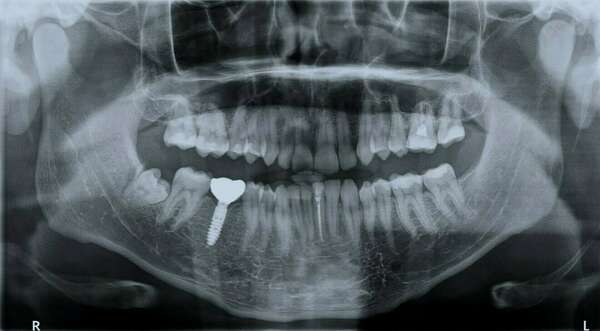

Un appareil orthodontique Incognito est disposé sur la face interne des dents, complètement hors de vue.